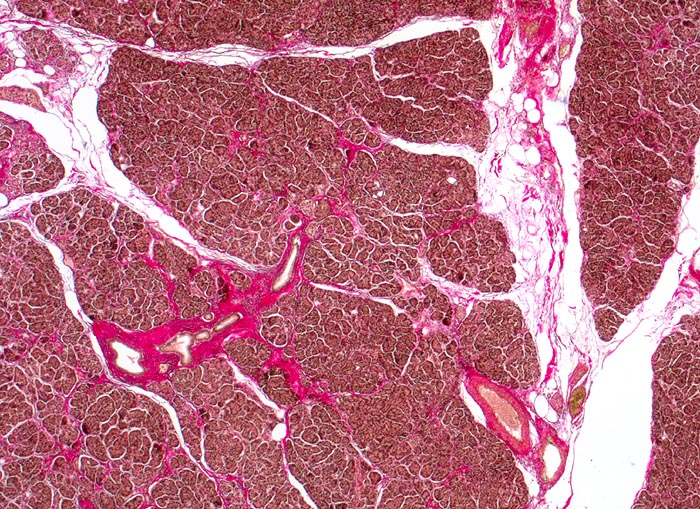

Morphologische Merkmale:

• Unregelmässige Anordnung der Drüsen (keine Läppchenarchitektur erkennbar).

• Kribriforme Drüsenformationen.

• Inkomplette Drüsen mit unvollständigen Lumina und Infiltration des Stromas durch Tumoreinzelzellen.

• Nekrotische Tumorzellen in den Drüsenlumina.

• Ausgeprägte Polymorphie und Hyperchromasie der Tumorzellkerne.

• Desmoplastisches Stroma.

• Rechts oben Reste von nicht neoplastischem Pankreasparenchym mit fokaler chronisch obstruktiver Pankreatitis als Folge von tumorbedingten Gangobstruktionen: Vollständige Atrophie des exokrinen Pankreas bei erhaltenen Inseln. Ersatz des atrophen Parenchyms durch Fibrose. Chronisches Entzündungsinfiltrat.